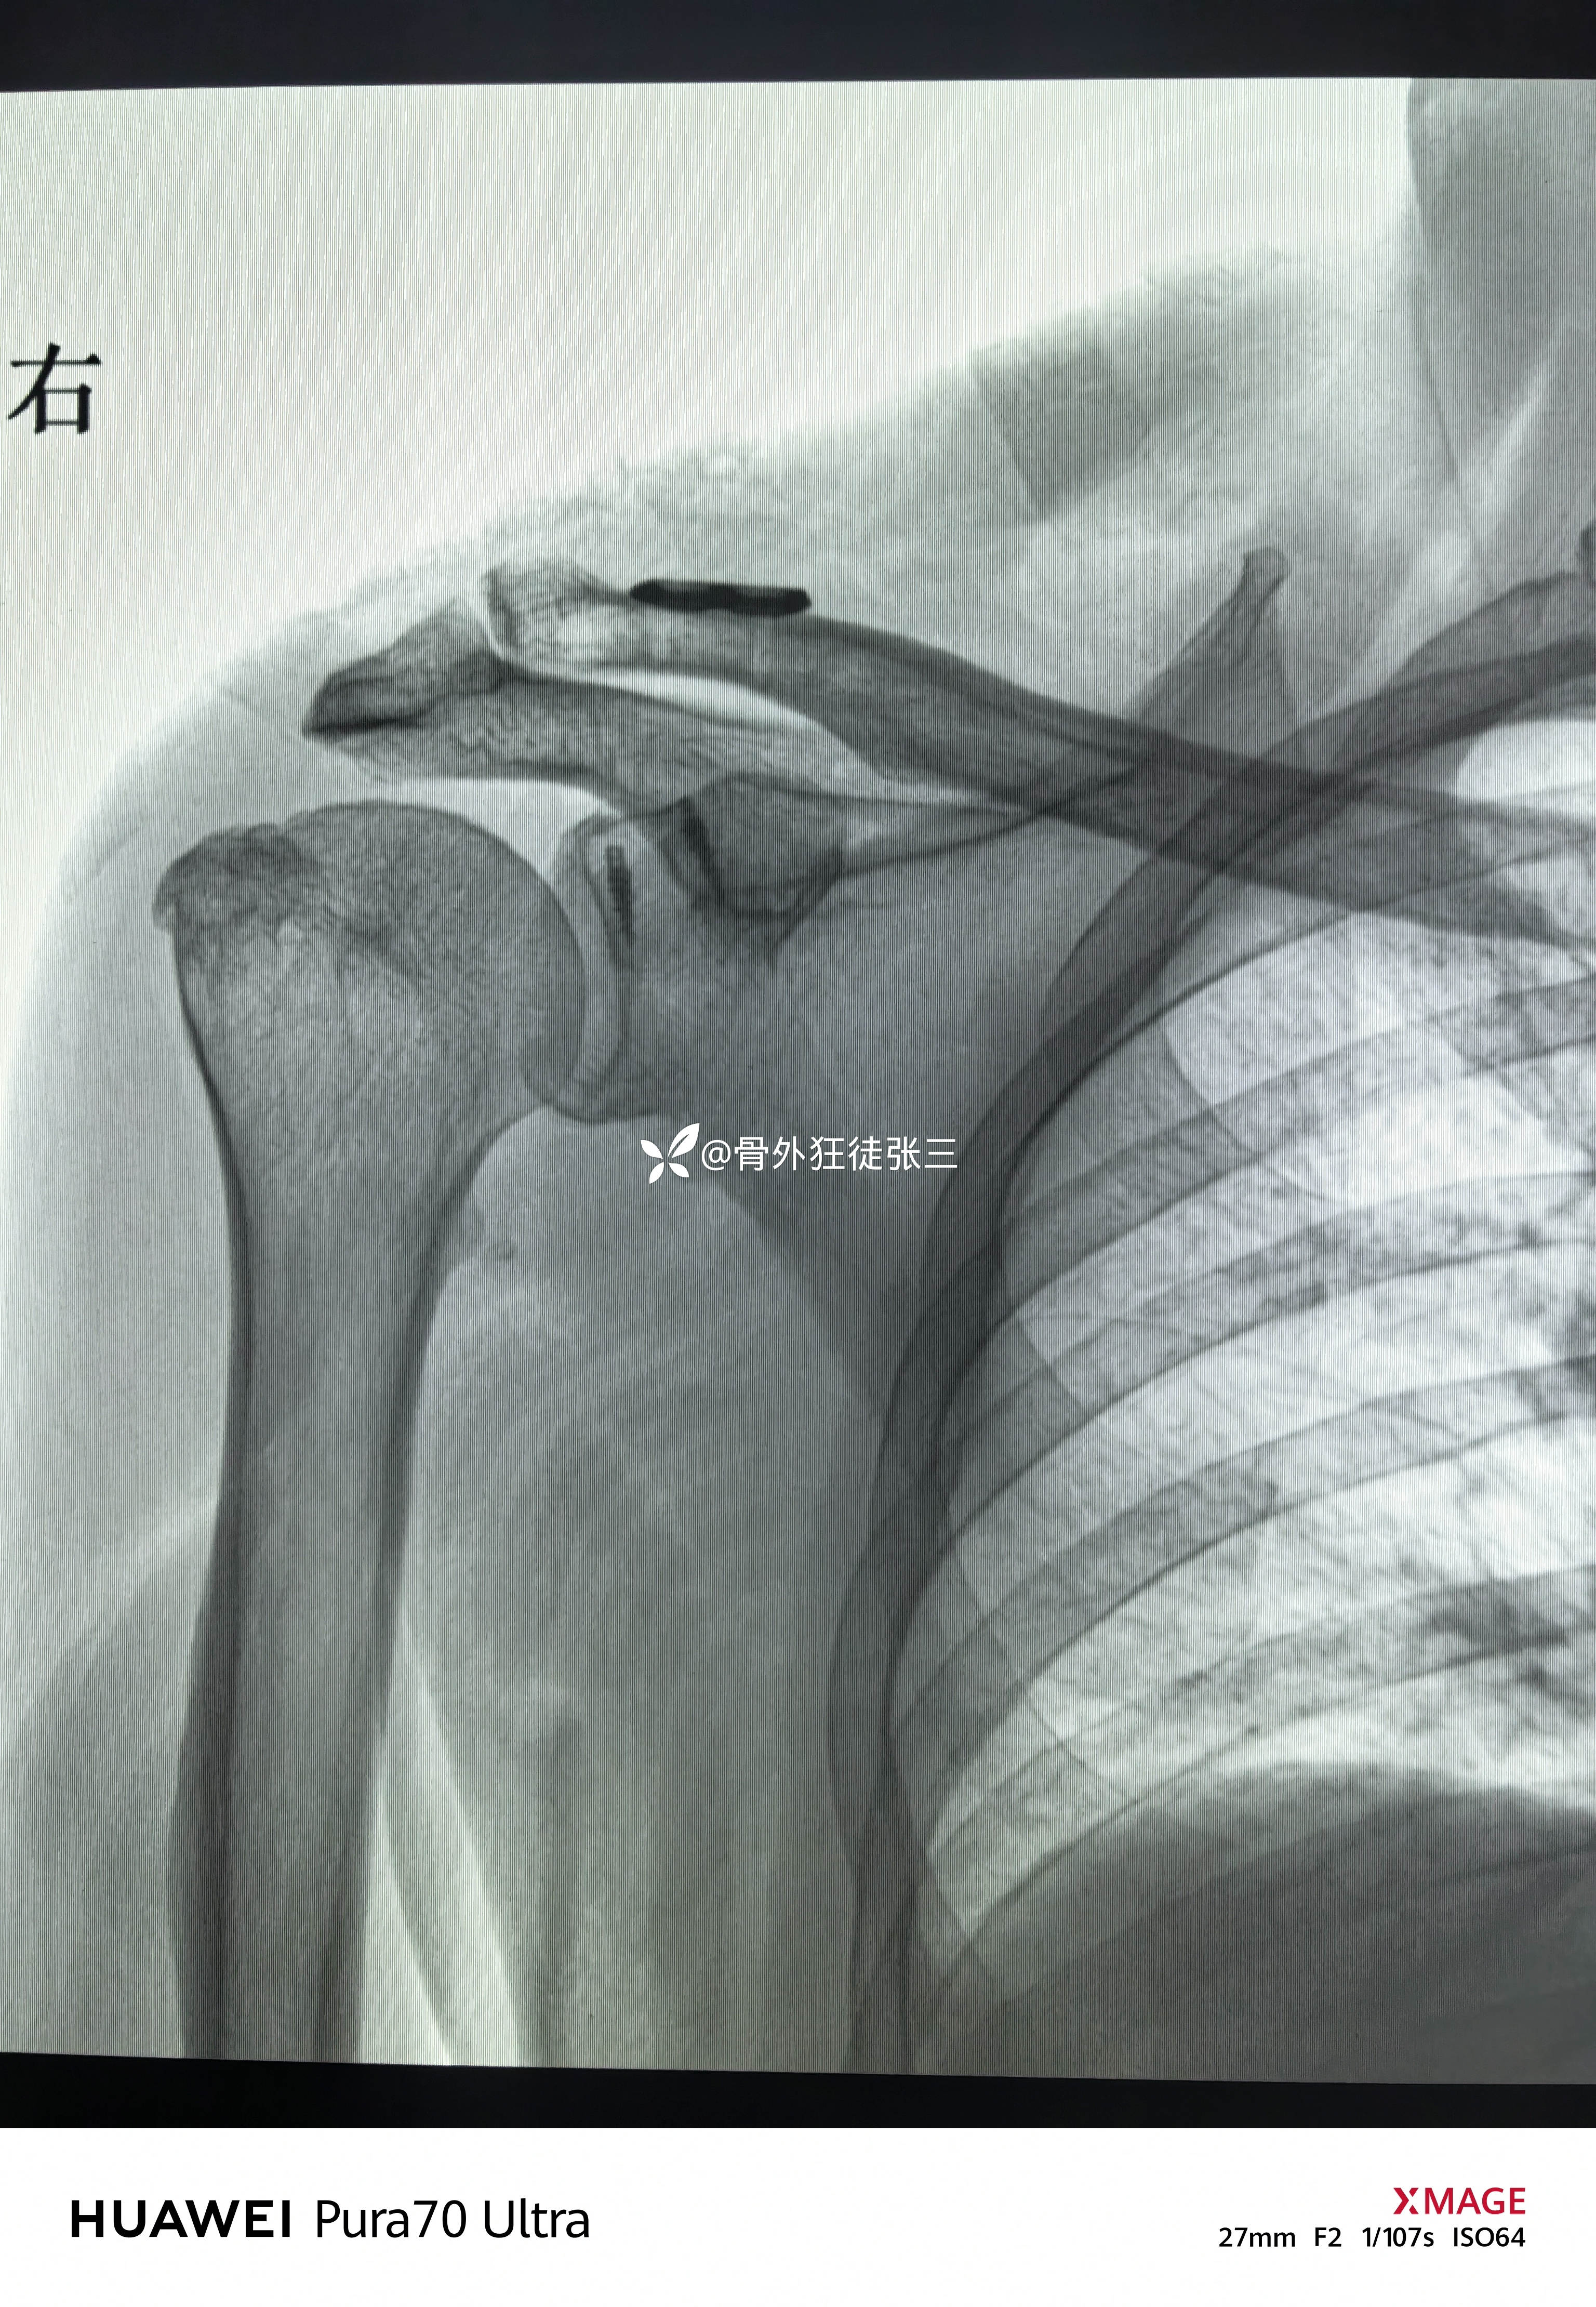

简易袢板——肩锁关节脱位可以更简单。

主诉:摔伤右肩关节致疼痛、活动受限1天。

右肩锁关节脱位(Tossy分型III型)